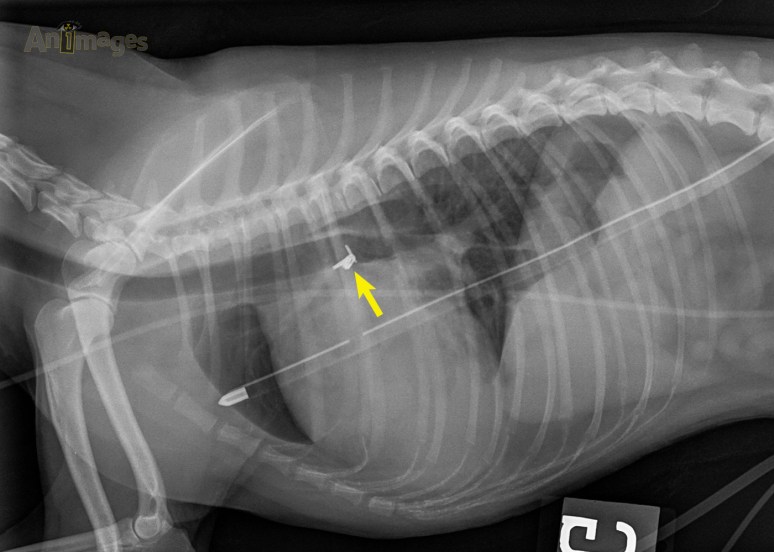

Cette pathologie fut confirmée par échographie et le canal fut fermé chirurgicalement. Sur les radiographies de suivi post-opératoire (ci-bas), on remarque les agraffes métalliques placées autour du canal pour le refermer. Notez aussi que la cardiomégalie et la sur-circulation pulmonaire sont en partie résolues.